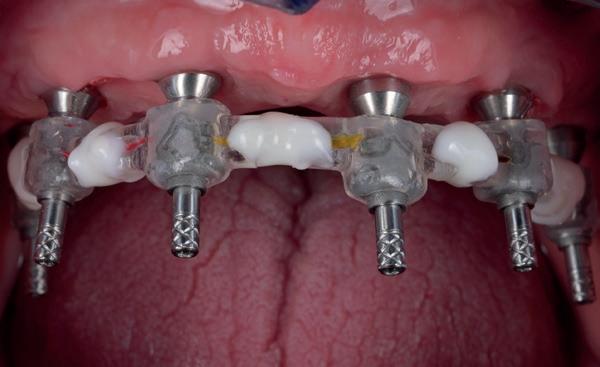

Zitting 4 plaatsen PMMA brug & multi-unit abutments

Wanneer de tijdelijke brug retour komt, dienen eerst de healing abutments verwijderd te worden en de implantaten uitgespoeld te worden met Blue M spoelmiddel in een monoject. De brug paste niet direct op de interne verbindingen van de implantaten, omdat deze daarvoor niet parallel genoeg stonden, omdat de kaak in een curve liep. Daarom wordt over het algemeen gekozen voor multi-unit abutments die op de implantaten worden gedraaid. Hierdoor wordt de brug op coronaal hoger niveau geplaatst en door de multi-unit abutments wordt een open inzetrichting verkregen.

De PMMA tijdelijke brug werd direct op de multi-unit abutments geschroefd met kleine schroefjes. De schroefgaten van de brug werden afgesloten met teflontape en composiet. Indien nodig, kon er aan de PMMA brug de occlusie en articulatie geslepen worden. In deze casus was dat verder niet nodig. De

patiënt kon 2 maanden functioneren met de tijdelijke brug, waarna een kort consult werd gepland om te bespreken of hij tevreden was met de esthetiek en functie. Voor de patiënt hoefde niks veranderd te worden (afbeelding 11-14).

11. Tijdelijke PMMA-brug op model

12. Na plaatsen van multi-unit abutments

13. Na plaatsen tijdelijke brug op de implantaten

14. Portretfoto met tijdelijke brug